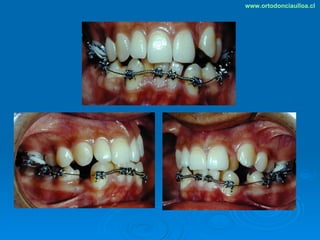

Este documento presenta dos casos clínicos de pacientes que recibieron tratamiento de ortodoncia. El primer caso fue de una paciente femenina de 14 años con apiñamiento dental y mordida cruzada que fue tratada mediante extracción de premolares y alineamiento dental. El segundo caso fue de un paciente masculino de 14 años con clase II esqueletal y desarmonía dentomaxilar que fue tratado con extracción de premolares y corrección de mordida. Ambos casos mostraron mejoría después de 3 años de tratamiento.